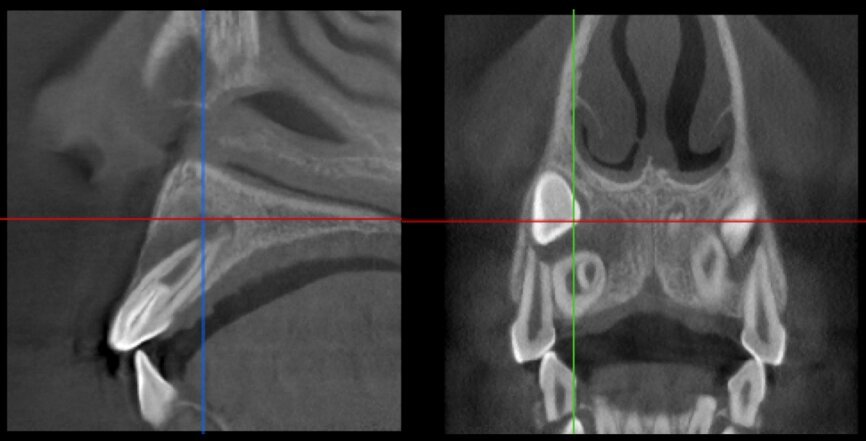

The case with which I would like to start my clinical review is a perfect example of how difficult it is to establish the origin of the patient’s symptoms on the basis of an intraoral radiograph alone. Not only does the 2D study fail to establish with certainty the presence of a lesion, but more importantly, it is impossible to establish the size, morphology and type of the lesion. An analysis of the 3D imaging, however, provides a clear picture of the clinical situation: the coronal and sagittal slices revealed the presence of a large lesion extending from the apex of the mesial root of this molar to the furcation, while the axial slices allow us to conduct a precise analysis of the endodontic anatomy and, in particular, the shape of the mesial root, which in this case was fused with the palatine root. A full overview of the case can, therefore, guide the decision-making process and direct the treatment plan towards a specific type of treatment (Figs. 1–4).